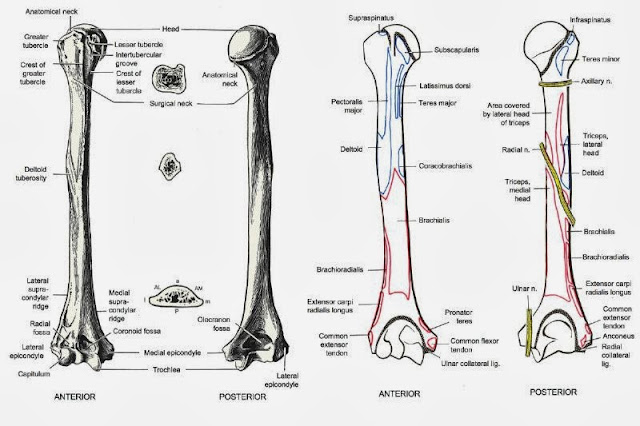

肱骨 Humerus 小小整理網站smallcollation

肱骨 Humerus 小小整理網站smallcollation

肱骨 Wikiwand

肱骨 肱骨 位於上臂 又叫上臂骨 上端有半球形的肱骨頭與肩胛骨的關節盂組 百科知識中文網

肱骨 维基百科 自由的百科全书